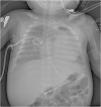

Radiografía a los 2 meses y medio de vida. Es la primera radiografía realizada a la paciente en la que ya se observa engrosamiento cortical, que es más evidente en las diáfisis de ambos húmeros (flecha), observándose la forma original de los huesos. También se observa engrosamiento de otros huesos como costillas, clavículas y escápulas.